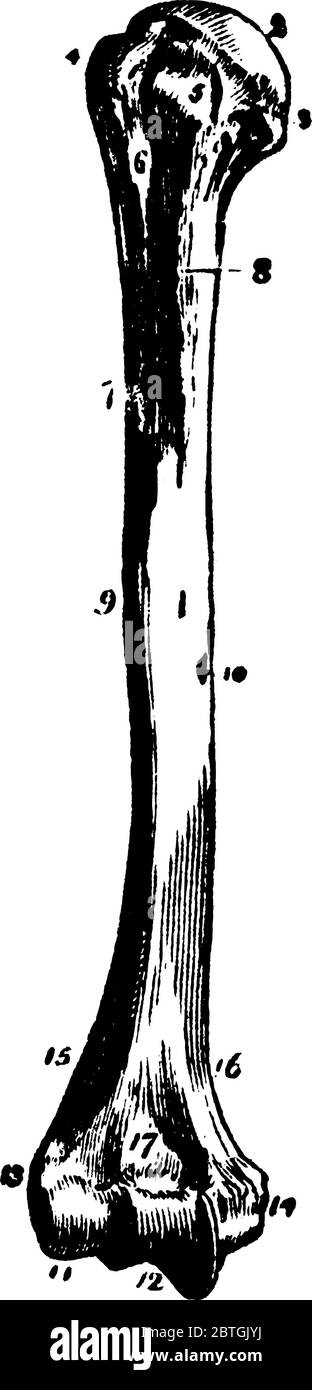

RF2BTGJYJ–Der Humerus ist ein langer Knochen des oberen Gliedes zwischen Ellenbogengelenk und Schulter, Vintage-Linie Zeichnung oder Gravur Illustration.

RF2BTHB20–Der Humerus ist ein langer Knochen des oberen Gliedes zwischen Ellenbogengelenk und Schulter, Vintage-Linie Zeichnung oder Gravur Illustration.